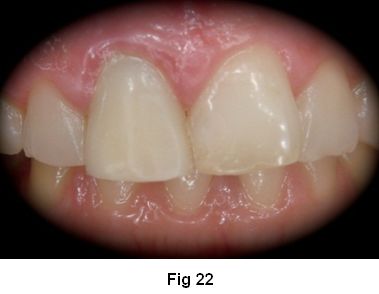

2. Confección de provisorio. (Fig. 22)